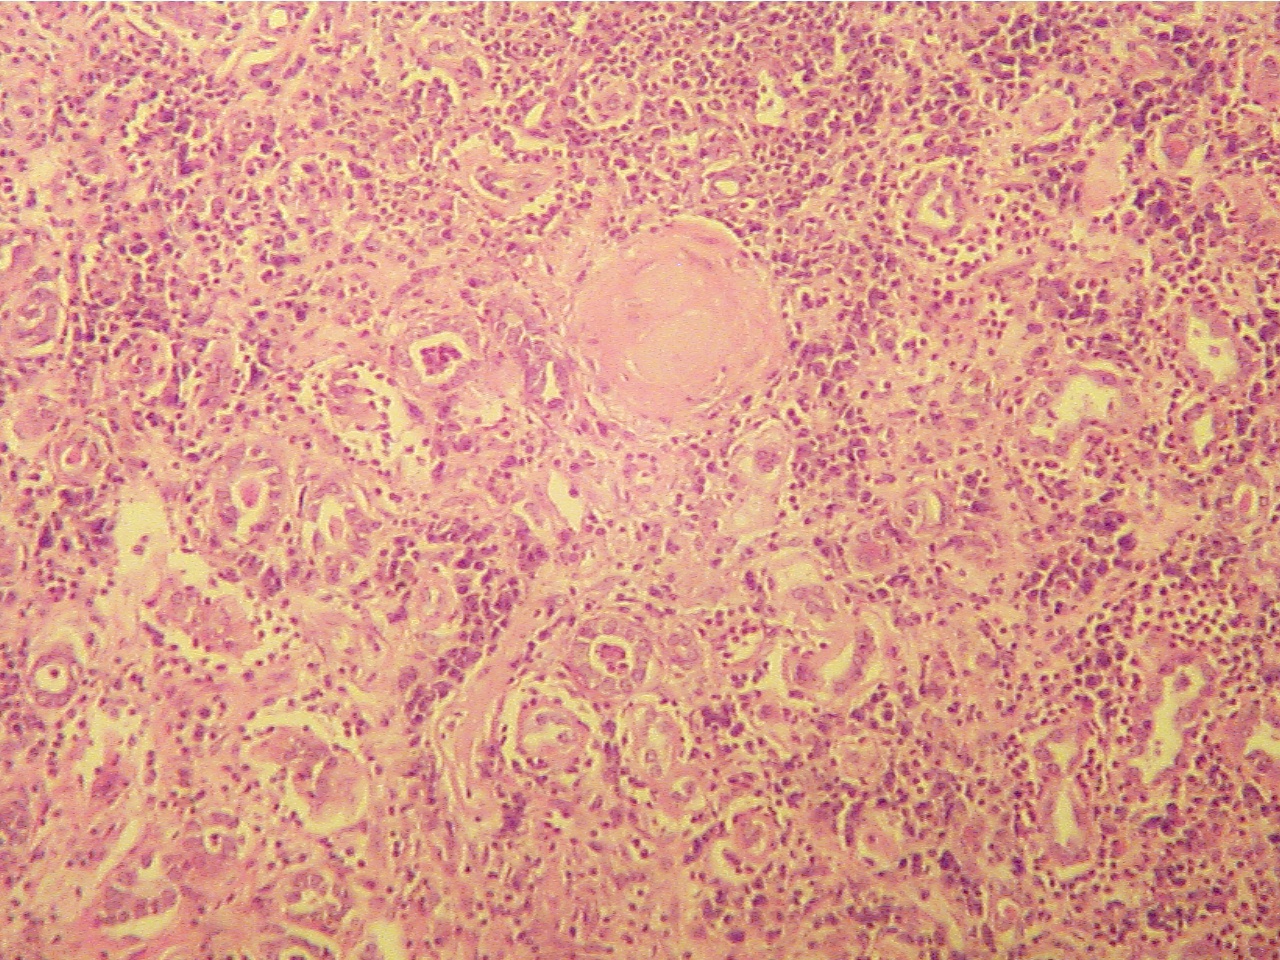

End-Stage Kidney - (Kidney in Diabetes - PH 1765)

(Be able to identify this slide as end stage kidney; identify normal glomeruli, abnormal glomeruli, tubules, and fibrotic inflammed area; and differentiate between this slide and slides showing normal kidney.)

Regardless of the starting point of each specific type of chronic renal disease, the end is the same, destruction of all parts of the nephron. This final stage is called end-stage kidney. This particular slide shows end-stage kidney due to diabetes. (pp. 713-715, Fig. 46-18)

Compare this slide with that of the normal kidney and with Fig. 46-11 on page 706 of the text. Note that both the glomeruli and tubules are abnormal. Many of the glomeruli are hyalinized (replaced by pink protein material) and many of the tubules show fibrosis. There is also blood present (RBCs) within the tubules.

End stage kidney (ESK) cortex (100X2.0)                                     End stage kidney (ESK) glomerulus  (320)

Hyalinized glomerulus (above center), few tubules                Hyalinized glomerulus (mostly solid pink with few

around glomerulus and throughout, inflammatory cells        dark blue nuclei) surrounded by small dark blue

and fibrosis (areas between structures).                                  inflammatory cells rather than tubules.